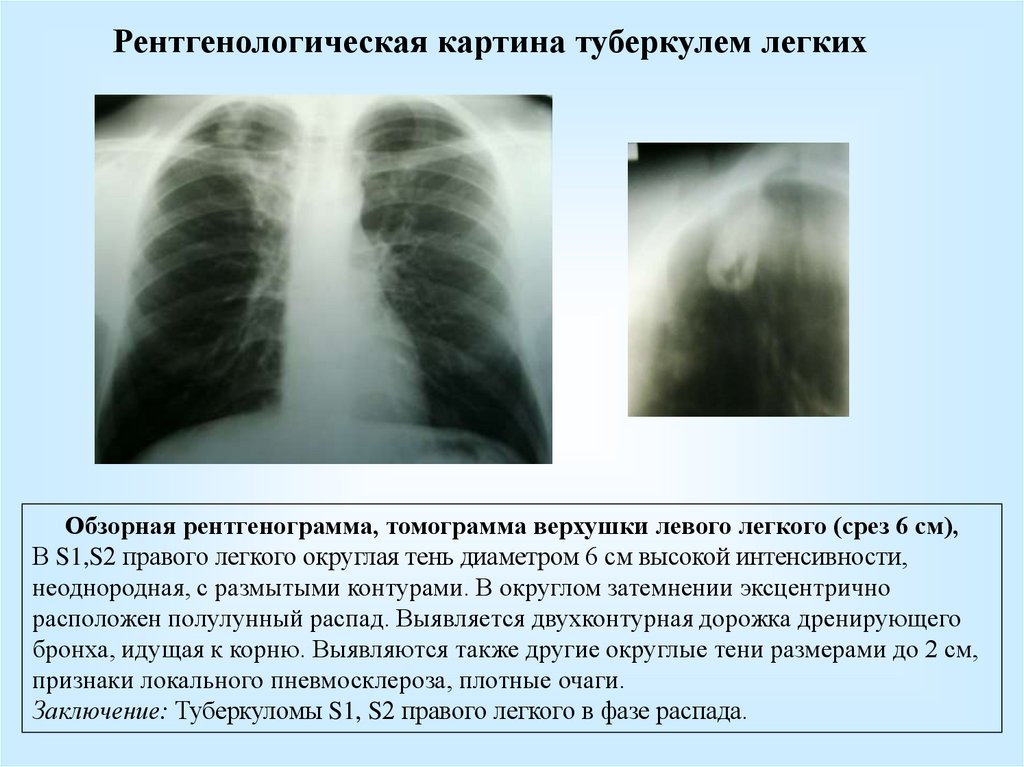

Очаговый и инфильтративный туберкулез презентация - 94 фото